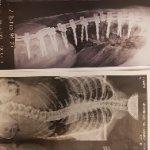

جراح مغز و اعصاب و ستون فقرات.دیسک کمر و دیسک گردن .عصب سیاتیک.درمان شکستگی مهره ها و جراحی تومورهای مغز و نخاع.درمان کمر درد و درد گردن مزمن لیزر دیسک کمر بدون نیاز به جراحی باز..تزریق داخل کمر.تزریق اینترا فورامینال و اعمال کم تهاجمی ستون فقرات.

گالری